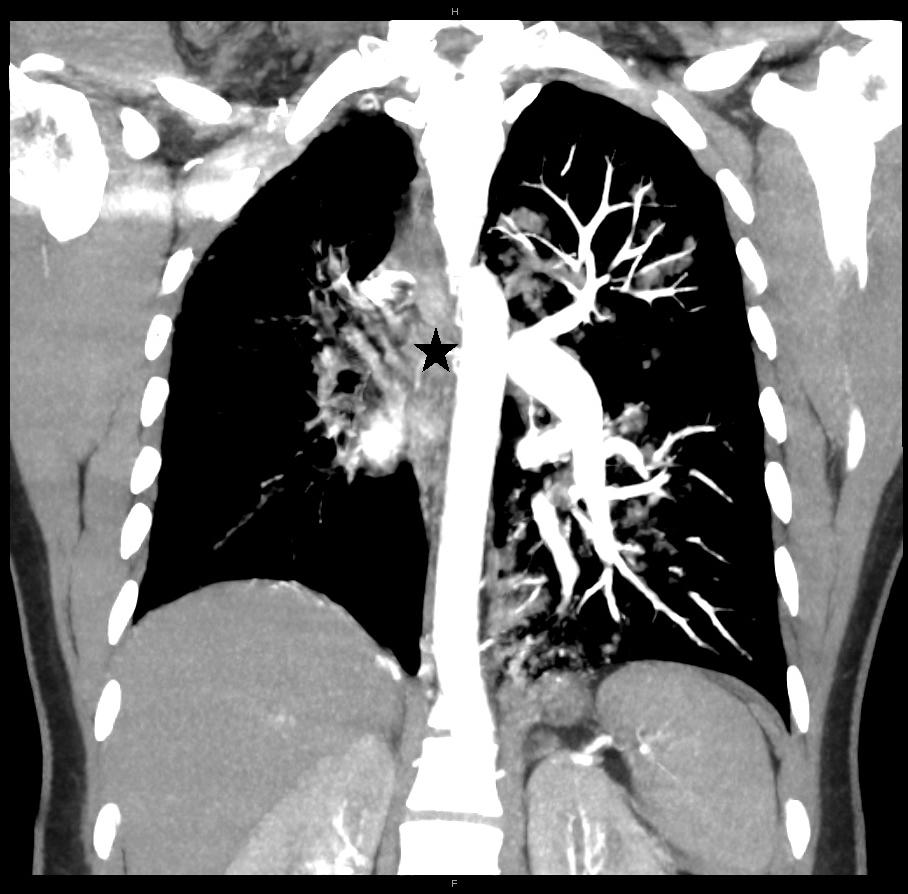

333 Absent Pulmonary Artery Presenting as High-Altitude Pulmonary Edema D Dllon, AT Smith

3 4% Ibuprofen 10/10 5 mL 0.25% bupivacaine 0/10